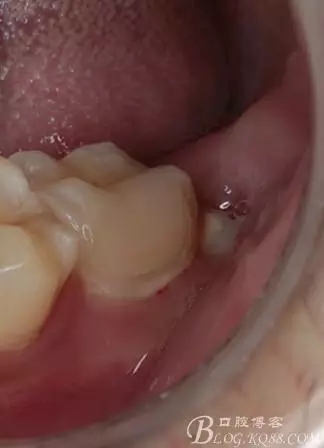

口腔檢查:37頰頜面齲洞,叩(+),探(+),冷熱測(cè)試與對(duì)照牙對(duì)比為敏感。17 27 47 均有不同程度齲壞,無明顯陽性體征。18 28 38 48 呈不同程度傾斜,38 48牙冠部分萌出。全口牙齒排列不整齊,口腔衛(wèi)生較差,牙石(++),部分牙齦發(fā)紅。X線檢查示37牙冠低密度影像累及牙髓,牙周間隙略增寬。

去除暫封物,拍照,比色。